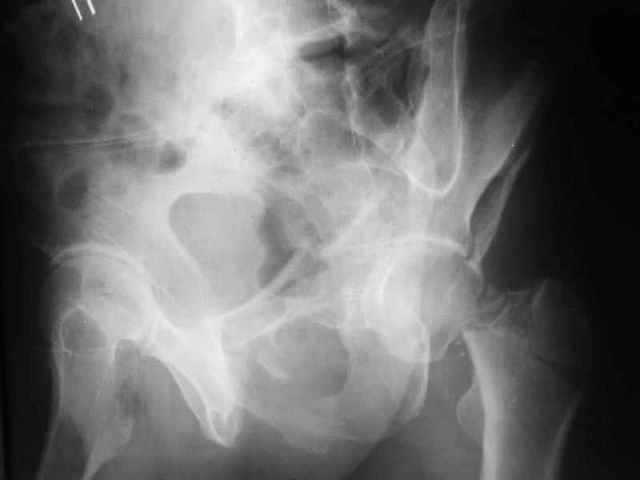

Больной 18 мая 2003 года в автоаварии получил перелом левой вертлужной впадины, вывих бедра. Госпитализирован в один из стационаров области.Вывих вправлен. В последствии бедро вывихивалось еще дважды. На консультацию был представлен снимок от 19.05.03г., больной переведен к нам 3.06.03г. Снимок при поступлении - перелом впадины, задне-верхний вывих бедра. 05.06.2003 г. выполнено открытое вправление вывиха левого бедра и остеосинтез стенки вертлужной впадины двумя винтами. Послеоперационный период без осложнений. Объем движений в левом тазобедренном суставе восстановился полностью. Выписан на амбулаторное лечение в удовлетворительном состоянии с рекомендациями 3 месяца ходить на костылях без нагрузки на оперированную конечность. На контрольных рентгенограммах левого тазобедренного сустава 13.10.2003 г. - признаки консолидации перелома; плотность, форма головки и состояние суставных поверхностей удовлетворительные. Разрешена дозированная осевая нагрузка, на конечность с использованием дополнительной опоры. 19.12.2003 г. больной обратился с жалобами на боли в левом тазобедренном суставе. На рентгенограммах левого тазобедренного сустава 19.12.2003 г., 20.02.04г. - асептичекий некроз головки бедра. 5.04.04г. - эндопротез. Сейчас ходит без трости, не хромает. Особенность эндопротезирования - при удалении винтов прослежена линия перелома заднего края впадины и предложено установить чашку несколько меньшего диаметра, чтобы она была покрыта несломанной частью.